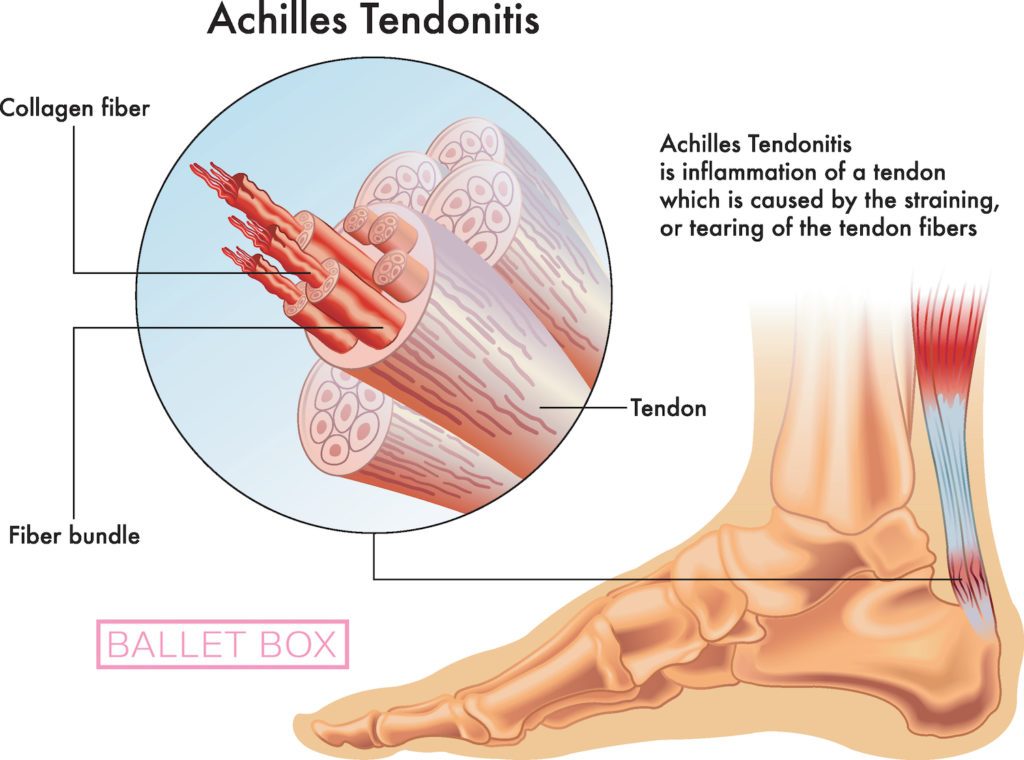

Тендинит Ахиллова сухожилия: симптомы и лечение

Раздел: Картинки на заметку